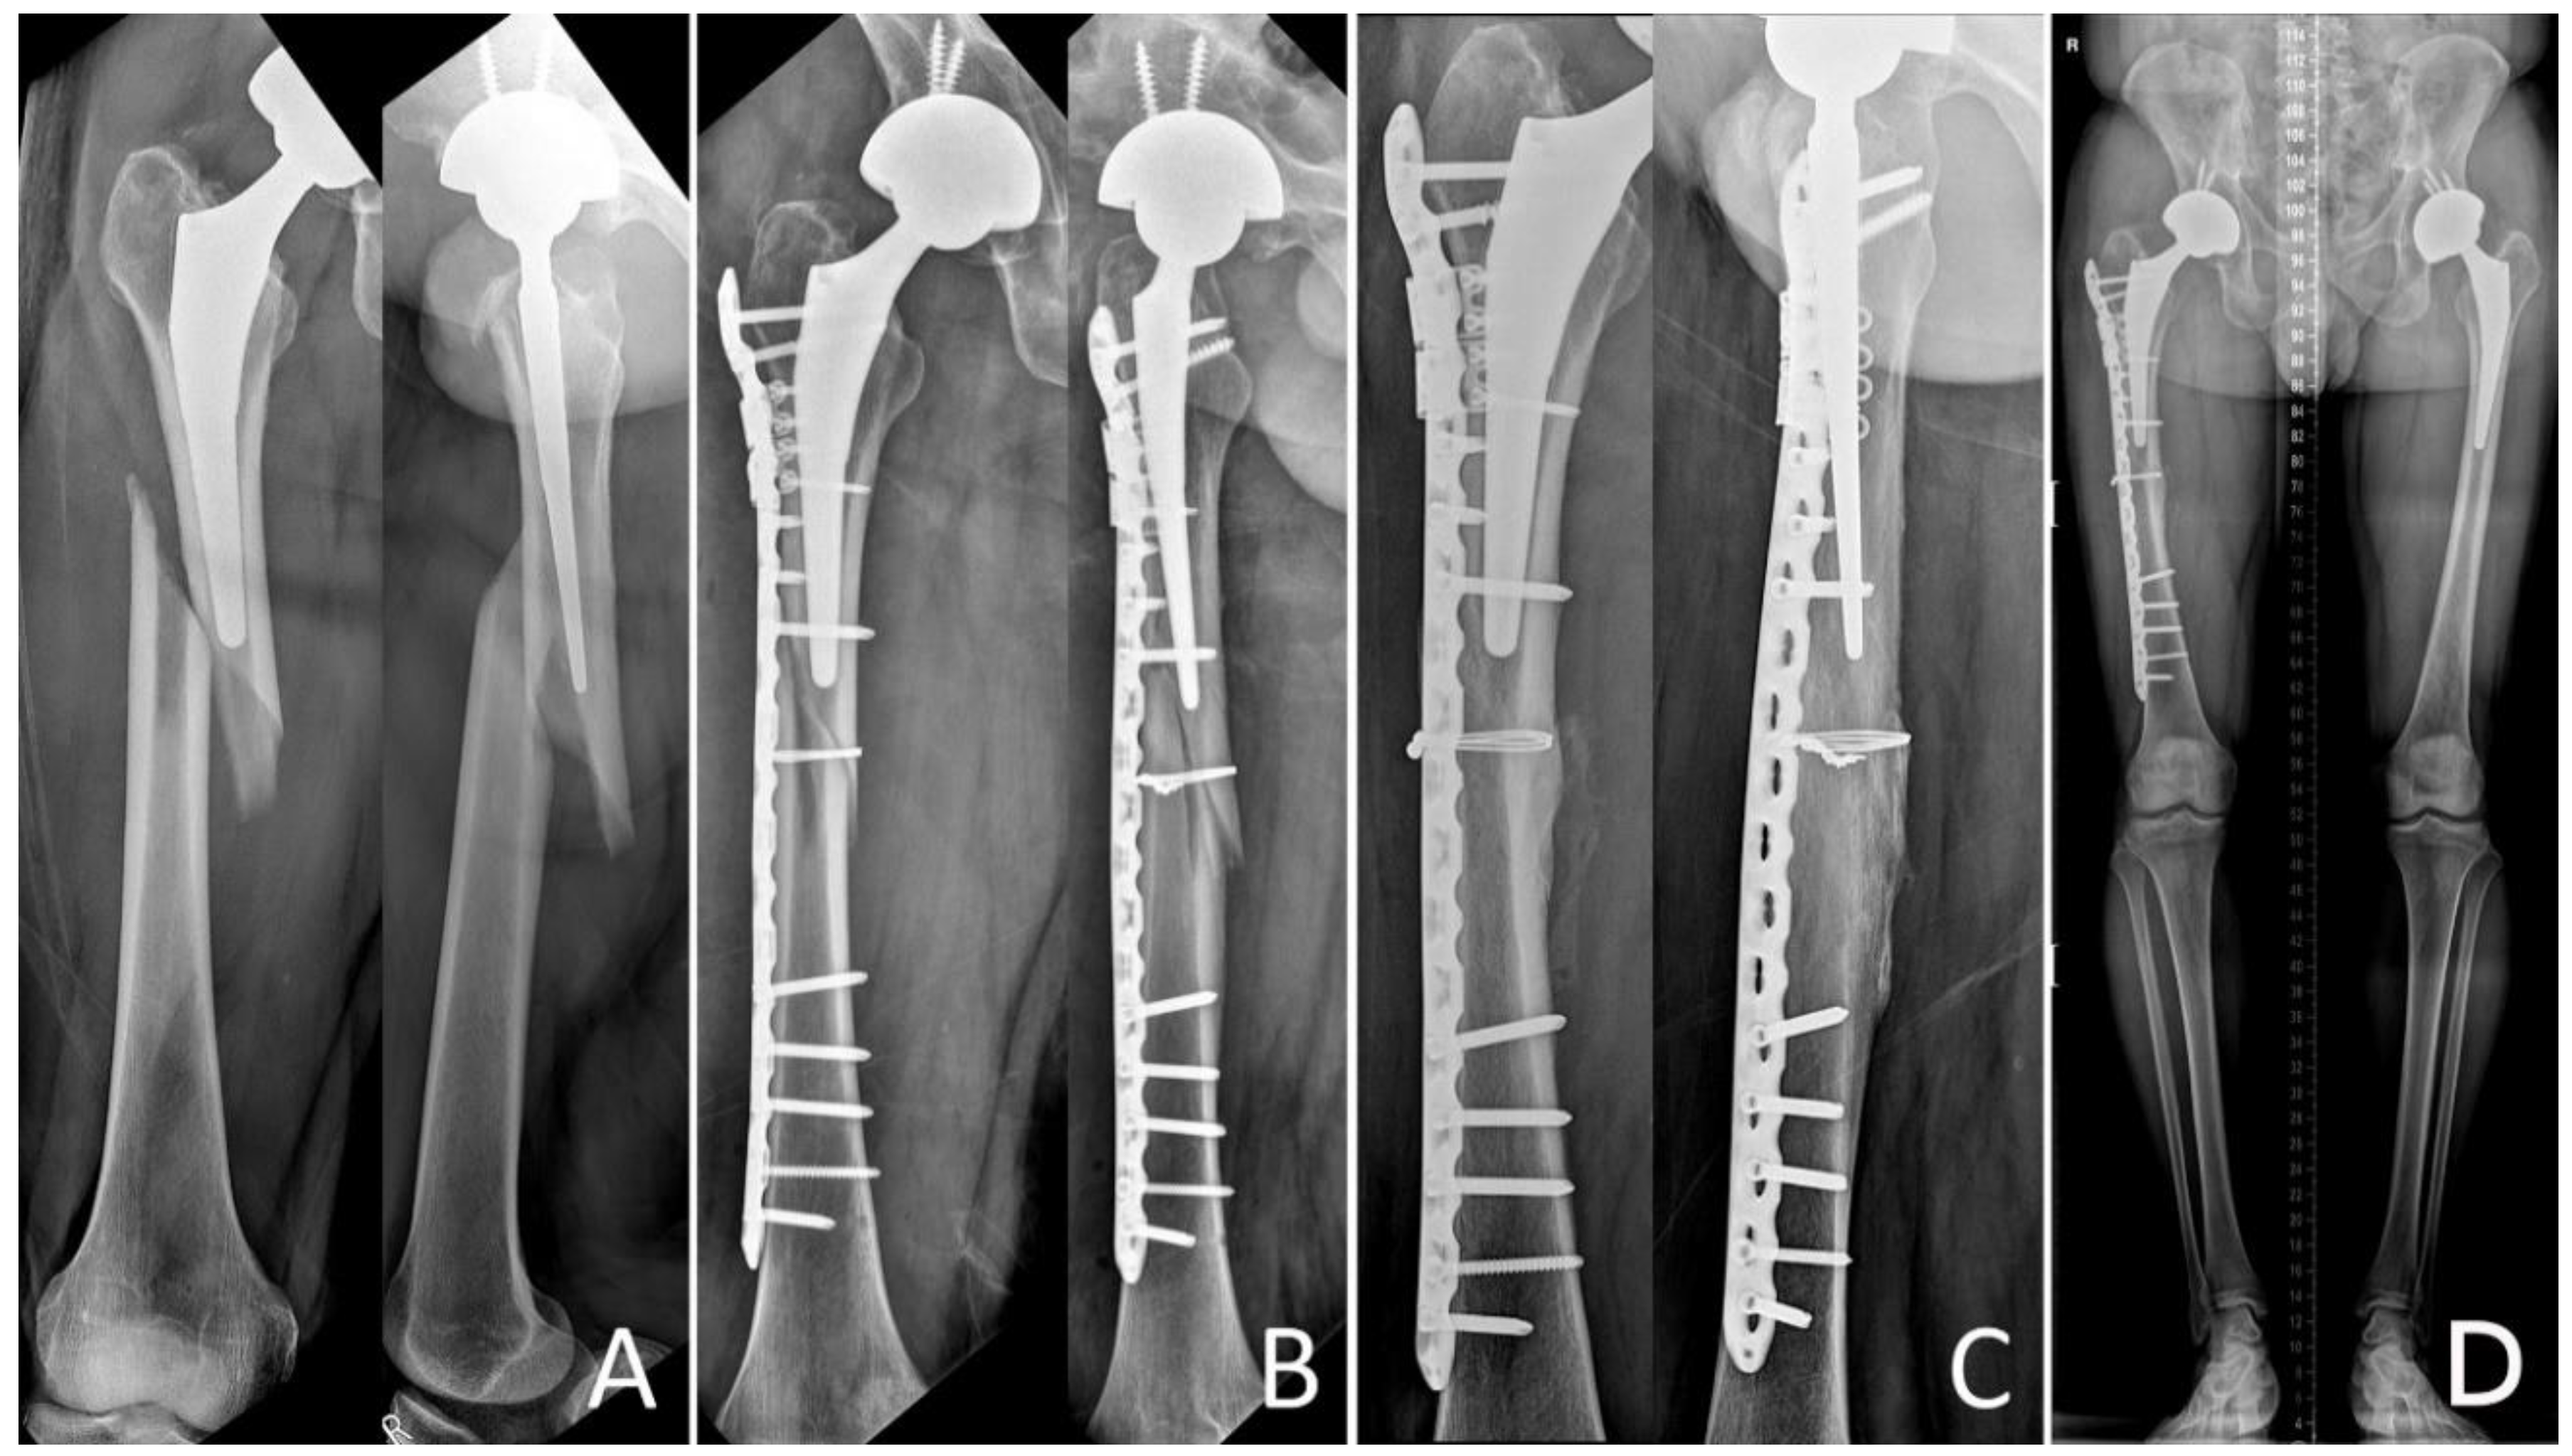

Surgery was performed according to the location and pattern of the fracture using minimally invasive plate osteosynthesis (MIPO) in 32 patients, and ORIF in 31 patients. Further, the patients who had Vancouver B1 fractures were operated on an orthopedic fracture table and traction was applied through a boot; patients with Vancouver C fractures were operated on a radiolucent table. Two incisions were made in the proximal and distal femur along the marking line while excluding the fracture site in case of MIPO technique. LCP was slipped into the submuscular supra-periosteal position and reduction in the fracture site was attempted indirectly by fluoroscopically guided external maneuvering to include less damage to the soft tissue and preserve periosteal circulation in the fractured bone [

11]. While maintaining the reduction status, distal and proximal positioning screws were fixed. To avoid the stress build-up between the prosthesis and the LCP, both the devices were overlapped. For reducing the risk of fixation failure, only 3–4 screws were inserted in each fragment to maintain proper distance between the stress centers on the plate. This aided in reducing the stress while pulling out screws and distributed the stress on the center of the plate at the fracture site [

5,

6]. Additional fixation was carried out using a locking attachment plate (Synthes, Oberdorf, Switzerland) or cables when bicortical screw fixation was impossible due to proximal femoral prosthesis (

Figure 2).

The direct lateral approach was used for the plate fixation in the case of the ORIF technique depending on the fracture location. The iliotibial band was incised, and the vastus lateralis was elevated from the posterior fascia. The periosteal exposure was limited to the fracture only to allow reduction. The plate was directly fixed to the bone after anatomical reduction.